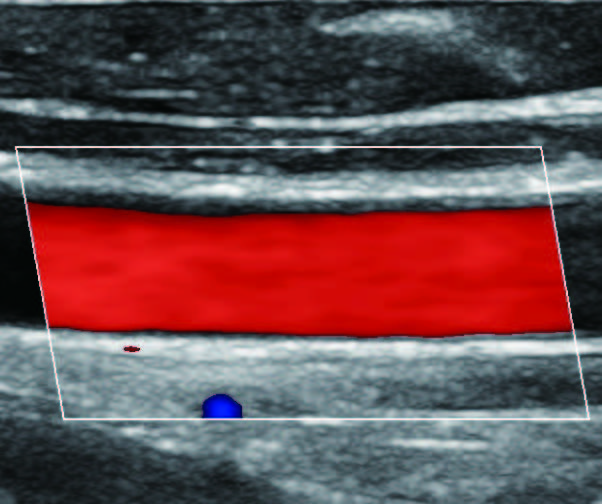

На изображениях, приведенных ниже показаны примеры из клинической практики врачей ультразвуковой диагностики, полученные в процессе апробирования прибора Mindray Resona 7. Приводится наглядные примеры сравнения традиционного режима ЦДК и режима V Flow (Vector Flow).

Изображен ламинарный поток сонной артерии. В режиме ЦДК отсутствует информация о профиле ламинарного потока. Режим V Flow визуализирует не только скоростные характеристики с помощью цветных стрелок, но и предоставляет данные о профиле ламинарного потока (быстрый поток в центре и медленный вблизи стенок сосуда).